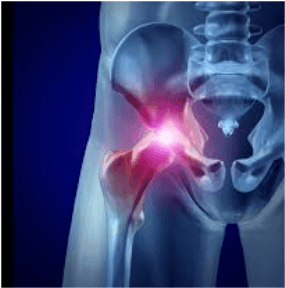

Kalça kireçlenmesi, kalça ekleminin kıkırdak dokusunun zamanla yıpranması, incelmesi ve bozulmasıdır. Bu süreçte kemikler birbirine sürter, ağrı, sertlik, şişlik ve hareket kısıtlılığı ortaya çıkar. Tedavi edilmezse hareket kabiliyeti ciddi şekilde azalabilir. Kalça kireçlenmesi, kalça ekleminde yapısal ve fonksiyonel değişikliklerin eşlik ettiği ilerleyici harabiyet ve eklem kıkırdağı kaybı ile karakterize yaygın görülen kalça eklemini bozan bir eklem hastalığıdır. İlerleyen yaş, aşırı kilo, yoğun fiziksel aktivite, travmalar, doğuştan kalça çıkığı ve genetik faktörler hastalığın gelişiminde rol oynar. Kalça kireçlenmesi orta yaş ve yaşlı hastalarda da görülme eğilimi gösterir ve görülme sıklığı %10 civarındadır. Kalça ağrısı, tutukluk ve sınırlı hareket kabiliyeti ile hastaların yaşam kalitesini etkiler. Kalça kireçlenmesi tedavisi için ağrı kesici ilaçlar, Fizik Tedavi ve kalça eklemi içerisine kortikosteroid veya hyalüronik asit enjeksiyonları ağrıyı hafifletebilir. Ancak tüm bu sözü edilen geleneksel tedaviler yalnızca hastaların ağrılarını giderip, şikayetlerin bir nebze olsun azalmasını sağlayabilmektedir. Hastalığın ilerlemesini ve sonuçta total kalça protezine olan ihtiyacı geciktirememektedir. Özellikle, kalça eklemi kireçlenmesi olan genç hastalarda total kalça protezinden kaçınmak veya geciktirmek için cerrahi olmayan yeni tedavi seçenekleri önemi ortadır.

Son yıllarda, ameliyatsız kalça kireçlenmesi tedavisi yöntemi olarak karın bölgesi cilt altı yağ dokusundan elde edilen kök hücrelerle yapılan SVF Tedavisi yeni bir tıbbi tedavi olarak geliştirilmiştir. Kök hücreler, kişinin kedi yağ dokusundan kolaylıkla elde edilmesi, kıkırdak dokusuna dönüşme potansiyeli ve düşük komplikasyon riski gibi avantajlarından dolayı giderek daha popüler hale gelmiştir. Ayrıca, kalça eklemi kireçlenmesinin, kökeni kıkırdak hasarı ve inflamasyona dayandığından, kök hücreler büyüme faktörleri, sitokinler ve diğer maddeleri serbest bırakarak iyileştirici, onarıcı işlevleri yerine getirebilmektedir. Bu nedenle, kalçaya kök hücre tedavisi ile kalça eklemi etkili bir şekilde iyileştirilebilir, dokular arası yıkım etkisini azaltır. Kalça kireçlenmesine kök hücre tedavisi özellikleri nedeniyle yerel doku iyileşmesini uyarır ve bütünsel olarak kalça eklemini iyileştirir. Bu nedenlerle kök hücrelerle kalça kireçlenmesine ameliyatsız tedavi yöntemi öne çıkmaktadır.

Kalça osteoartriti, yani kalça kireçlenmesine kök hücre tedavisi ağrıyı azaltmayı, kalça eklemi kıkırdak kalınlığını artırmayı ve yaşam kalitesini iyileştirmeyi amaçlayan ameliyatsız kalça kireçlenmesi tedavisi şeklidir.